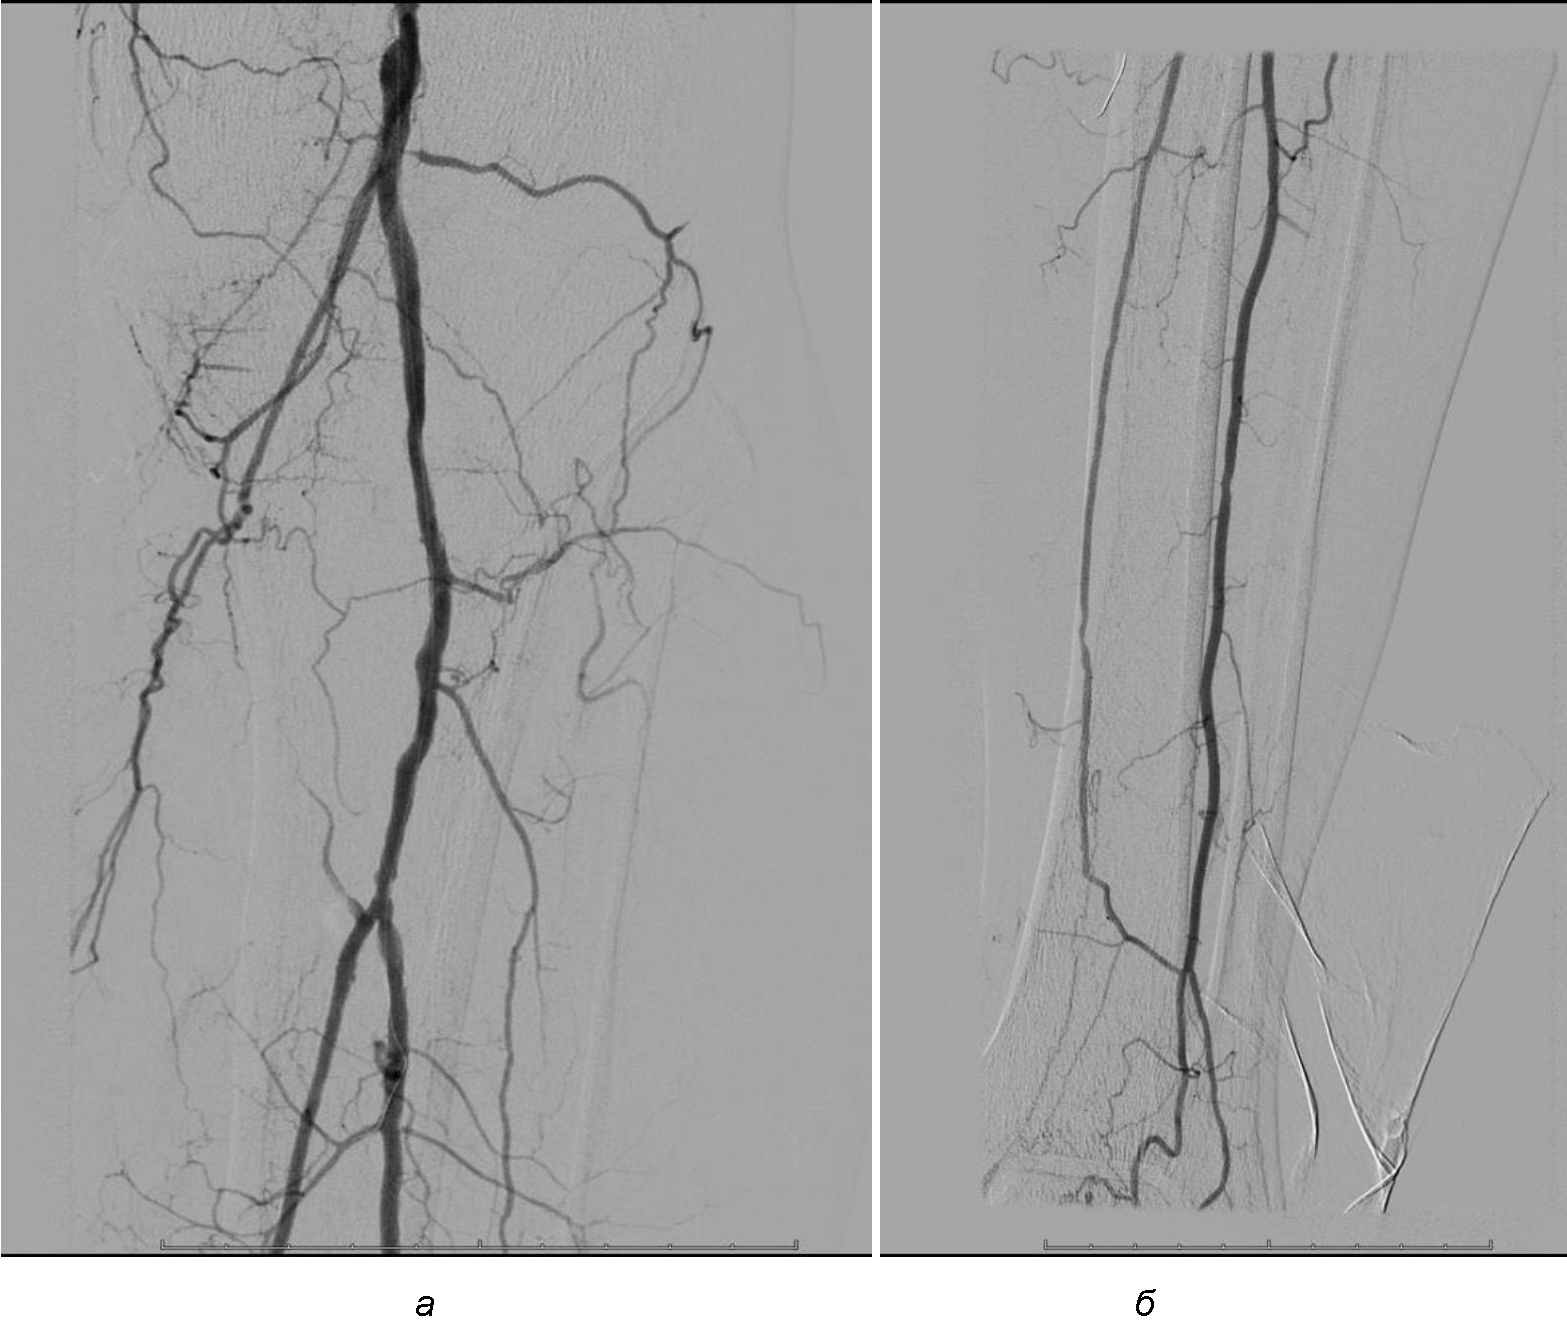

Операция. Транслюминальная баллонная ангиопластика (ТЛБАП) подколенной артерии, тибиоперонеального ствола слева. Под м/а выполнена пункция левой бедренной артерии, установлен интродьюсер 6 Fr. Выполнена селективная ангиграфия артерий левой нижней конечности при которой выявлена субокклюзия подколенной артерии и окклюзия тибиоперонеального ствола (рис. 1). Выполнена ТЛБАП в зоне субокклюзии баллоном 5,0 × 40 мм, давление 8 атм. В области тибиоперонеального ствола ТДБАП баллоном 3,0 мм × 100 мм, давление 10 атм. Получен хороший антеградный кровоток в подколенной, заднебольшеберцовой и малоберцовой артериях (рис. 2). Передняя большеберцовая артерия окклюзирована.

Рис. 2. Ангиограмма больной М. после ангиопластики. Восстановление магистрального кровотока в проксимальном (а) и дистальном (б) отделах голени

Послеоперационный период без осложнений. Со стороны раны положительная динамика, заживление вторичным натяжением.